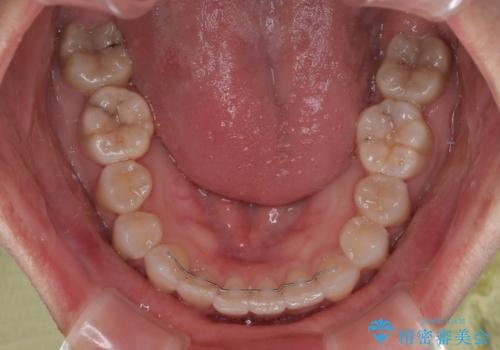

当初予定通り1年半ほどの治療期間で、非常に綺麗な歯列に仕上げることができました。

適合や携帯の悪いプラスチックのクラウンが装着されていたため、矯正治療後にオールセラミッククラウンによる補綴治療を行うこととしました。